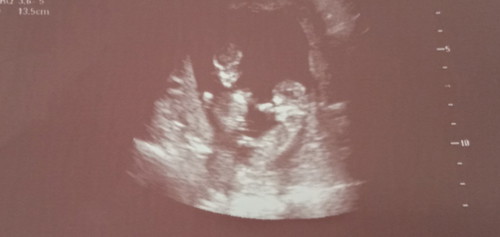

About Monochorionic Twin Pregnancy

Hi mgaaa mamsh na naka experience ng twin pregnancy and iisa lang ung bahay bata at inunan nila. Ano po ba mas okay? Manganak sa mga district or sa private po? And kung nakaya nyo po ba sila na normal or cs talaga? Kasi po ang package na binibigay nila sa akin ay 70k? kaso po ang hirap naman ipunin dahil no work no pay po kami parehas ni hubby ? Please pa'advise naman po ako. Thankyou ☹️